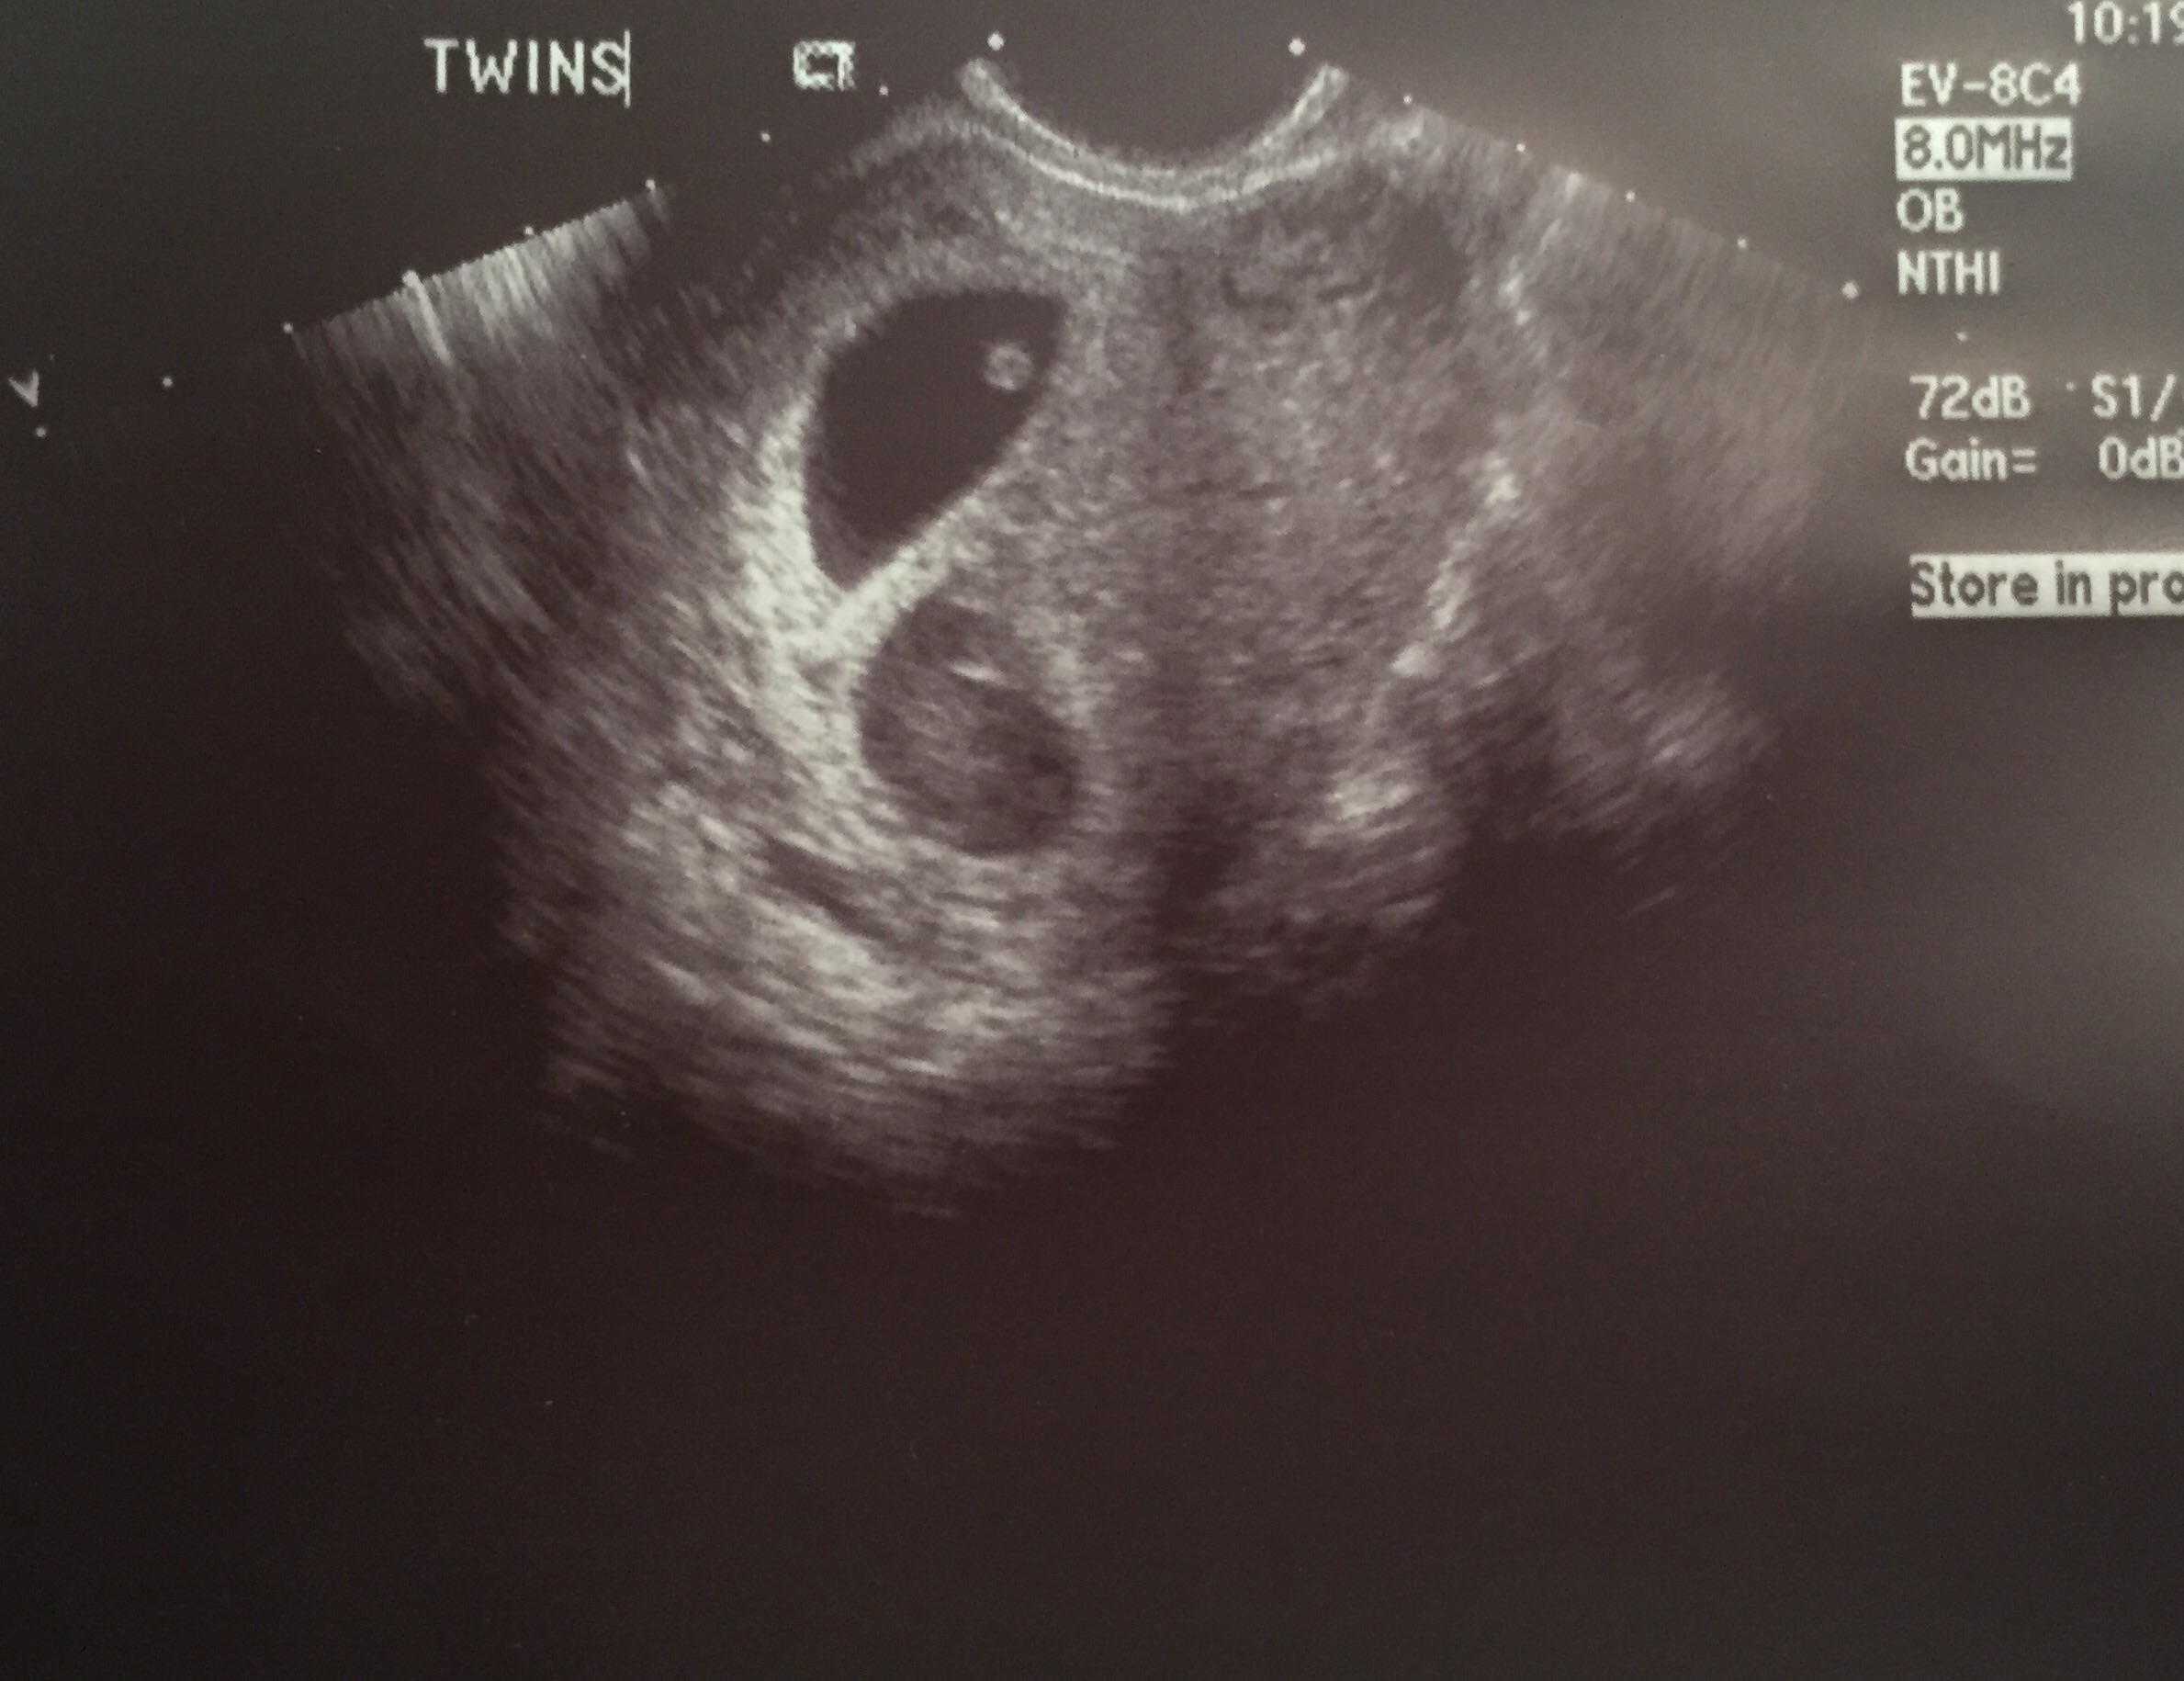

I've had one MC but I still won't go in for my 1st ultrasound until I'm 8+4

Me: 32 Hubby: 31

Emmett born February 2016

Expecting Baby #2 in August 2017